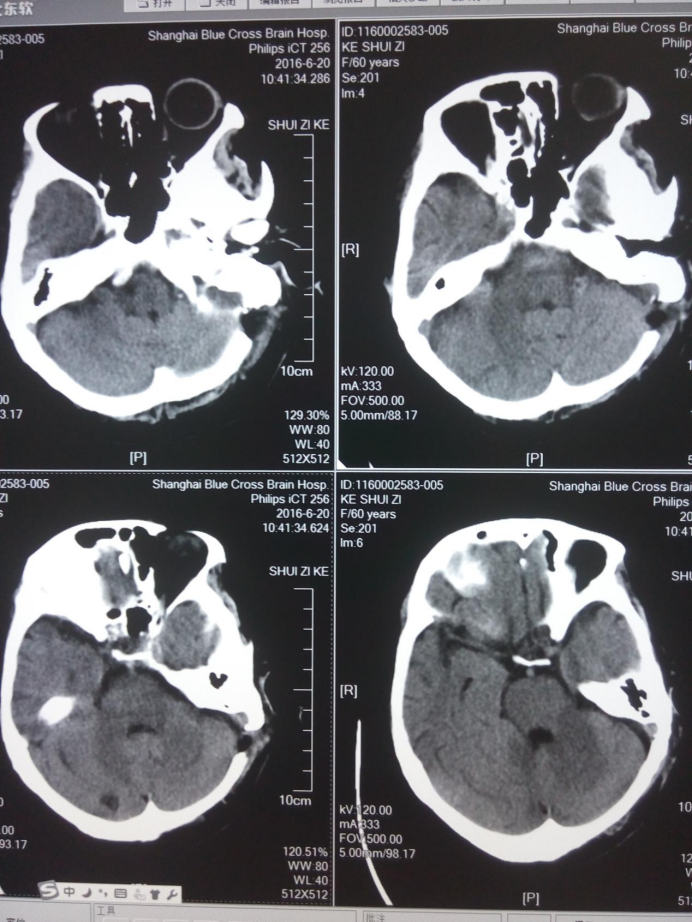

舌咽神经微血管减压术后头部CT检查